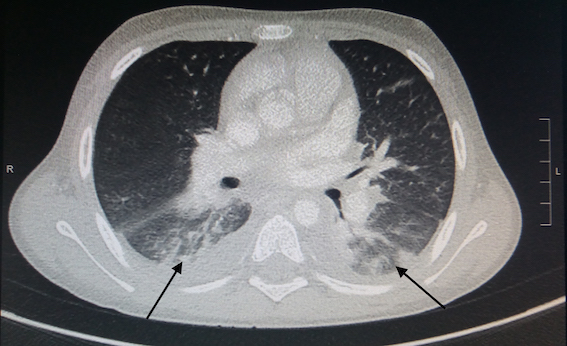

I dati di imaging sono riportati nella Tabella IV. La polmonite interstiziale postero-basale subpleurica è stato il reperto TC di maggiore riscontro (55% dei casi). Cinque pazienti hanno presentato versamento peritoneale associato o meno a linfoadenite mesenterica ed epatosplenomegalia. L’ecocardiogramma è stato eseguito in tutti i bambini, con evidenza di versamento pericardico nel 22% dei casi, insufficienza mitralica nel 33% e insufficienza tricuspidalica nel 22%. In un paziente è stato rilevato un aumento della birifrangenza coronarica. In nessun paziente è stata descritta una riduzione della frazione di eiezione. La cardio-RM è stata eseguita in post-dimissione nei 2 pazienti che hanno presentato bradicardia sinusale: in entrambi è stata confermata una funzione sistolica nella norma, in assenza di segni indicativi di edema e/o fibrosi del miocardio. La RM encefalo è stata eseguita in un paziente con sintomi neurologici, rilevando la presenza di lesioni compatibili con encefalomielite acuta disseminata (ADEM).

In accordo ai criteri diagnostici elencati in Tabella I, la diagnosi di MIS-C richiede la presenza del coinvolgimento di almeno 2 o più organi; gli esami strumentali svolgono quindi un ruolo fondamentale, soprattutto nel caso in cui l’interessamento d’organo sia clinicamente silente. Attualmente sono scarse le evidenze in letteratura riguardanti gli aspetti radiologici dei pazienti con MIS-C. I reperti toracici più frequentemente riportati sono la cardiomegalia, il coinvolgimento polmonare con aspetto a vetro smerigliato bilateralmente più o meno associato a consolidamento parenchimale (come osservato in 5 dei nostri pazienti - Figura 1), il versamento pleurico (presente anche in 4 dei nostri bambini), l’edema polmonare, l’embolia polmonare, il versamento pericardico (evidenziato altresì in 2 dei nostri bambini)13,14. Nei pazienti con MIS-C, l’imaging cardiaco (ecocardiografia e RM) può mostrare una ridotta frazione di eiezione del ventricolo sinistro, miocardite, pancardite, cardiomiopatia dilatativa e versamento pericardico15; un dato di rilievo nella nostra casistica è stato il riscontro di valvulopatia in 5 dei nostri pazienti (55%): abbiamo riscontrato 2 casi di insufficienza tricuspidalica e 3 di insufficienza mitralica, tutte di natura transitoria. Tra i reperti radiologici extratoracici, i riscontri più frequenti sono stati la linfoadenopatia mesenterica (rilevata in 2 dei nostri pazienti - Figura 2), l’ispessimento della parete intestinale con interessamento dell’ileo terminale e del cieco, l’epatomegalia, l’edema peri-portale (osservato anche in un nostro caso), l’edema della colecisti (come in uno dei nostri pazienti), i reni iperecogeni e gli infarti splenici15. La RM cerebrale nei pazienti con MIS-C può rilevare: ictus ischemico, encefalite, ADEM (rilevata anche nella nostra casistica - Figura 3) o leucoencefalite emorragica acuta15.